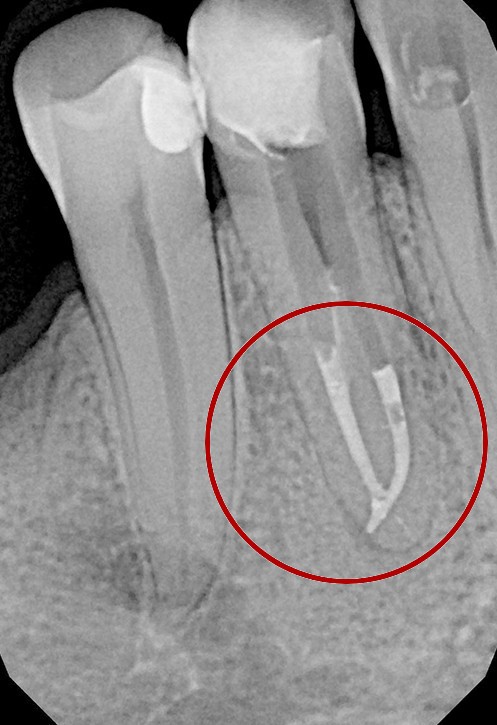

W przypadku zaawansowanych postaci zapaleń miazgi oraz zapalenia tkanek okołowierzchołkowych obraz radiologiczny jest warunkiem rozpoznania. W takiej sytuacji standardem diagnostycznym są zdjęcia przylegające zęba, często wykonywane przy użyciu radiowizjografii na fotelu stomatologicznym w trakcie leczenia zęba. Przydatne jest również badanie RTG OPG pantomograficzne, które pokazuje w dwuwymiarowym obrazie zarówno uzębienie, jak i cały układ kostny szczęki oraz żuchwy.

Najczęstsze przyczyny utrudnień lub niepowodzenia leczenia to pozostawione w kanałach zębów złamane narzędzia endodontyczne po uprzednim leczeniu, obliteracja, czyli bardzo słaba drożność kanałów korzeniowych lub wręcz jej brak, do której dochodzi na skutek przewlekłych stanów zapalnych miazgi, czy wreszcie niestandardowa anatomia zęba.

Konieczność powtórnego leczenia endodontycznego może zaistnieć w sytuacji, gdy kanały zęba nie zostały wypełnione do ich anatomicznego wierzchołka lub w trakcie leczenia doszło do złamania i pozostawienia ułamanego narzędzia w świetle kanału korzeniowego. O konieczności powtórnego leczenia endodontycznego może również zadecydować zmiana zapalna przy wierzchołku korzenia, która jest widoczna jedynie na obrazie kontrolnego zdjęcia rtg.